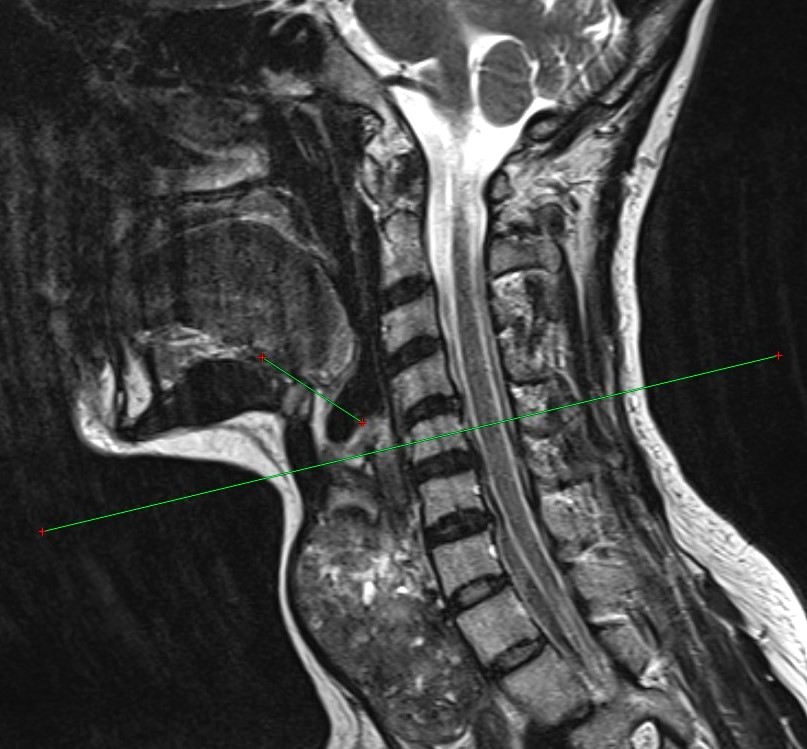

Щитовидная железа при заболеваниях нередко требует хирургического вмешательства, которое остаётся основным подходом к лечению. Однако существующие методы перевязки верхнего полюса органа ориентируются исключительно на его стандартные размеры, не принимая во внимание возможное увеличение щитовидной железы и связанные с этим анатомические изменения. Новый метод решает эту проблему, позволяя с высокой точностью определять толщину и уровень расположения верхнего полюса увеличенного органа.

Преимущество разработанной техники заключается в её способности снижать риск интраоперационных и постоперационных осложнений, таких как кровотечение или повреждение верхнего гортанного нерва. Ещё одним значимым плюсом является простота метода, что делает его доступным для внедрения в стационарах, оборудованных компьютерным томографом.